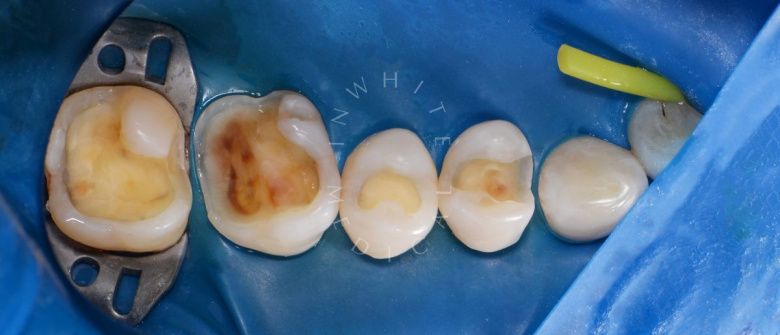

Лечение фиссурного кариеса под увеличением

Стоматология Москва лучшие клиники. Лечение фиссурного кариеса под увеличением - до процедуры